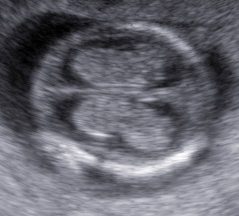

Cráneo

La determinación de la normalidad anatómica depende de la etapa del desarrollo en la que se pretende estudiar en contenido encefálico y del momento de aparición de las anomalías posibles; además, a diferencia de otros órganos cuya estructura madura es bastante estable y resistente a agresiones durante el embarazo, el contenido craneal puede verse afectado en cualquier etapa del embarazo, durante el nacimiento y en vida posnatal.